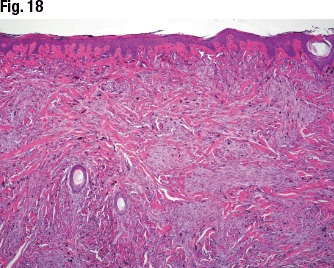

She presented the case of a 19-year-old male with a pigmented nodule on his scalp. Large hypercellular melanocytic proliferation with uniform pigmentation is seen in Fig. 17 and elongation of rete ridges and small junctional component of the melanocytic proliferations in Fig. 18. “We found some of the cells showed very small nucleoli,” Dr. Aung said (Fig. 19). Ki67 staining showed a low to absent proliferative rate. HMB-45 showed diffuse positivity.